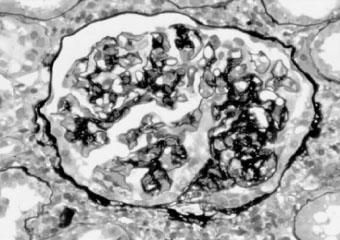

光镜下,FSGS特征性改变是受累的肾小球(<50%)内出现散在节段性分布的毛细血管袢(<50%毛细血管袢)塌陷闭塞,代之以无细胞结构的基质样物质及透明样物质增生,而未累及的节段光镜下相对正常(图2—6)。以皮质近髓部位的肾单位常见。毛细血管壁内可见泡沫细胞,脏层上皮细胞肥大,毛细血管袢与Bowman囊粘连。有时可见肾小管萎缩、间质纤维化也呈灶性分布。肾小动脉内膜出现玻璃样物质沉积,小动脉透明变性,无细胞增生反应。肾小球硬化区节段性IgM、C3积聚,其位置相当于血浆蛋白渗出部位,一般认为是非免疫“滞留”的结果。肾小管蛋白染色常阳性,可能是重吸收的蛋白。

图2—6 局灶节段性肾小球硬化(PASM x400)